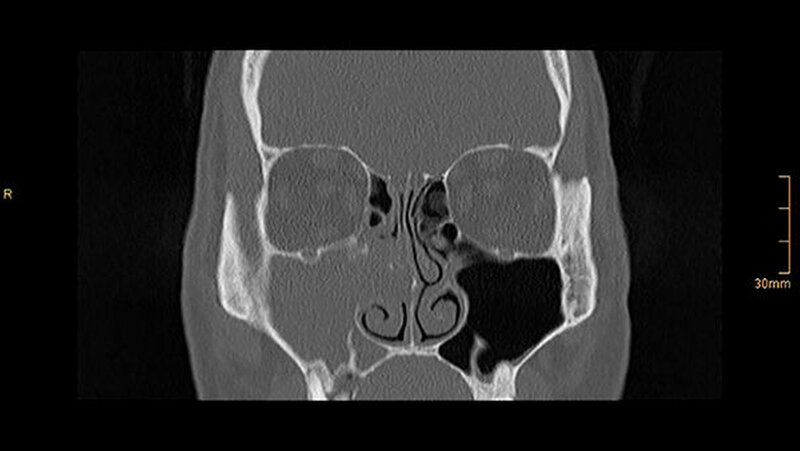

Die CT-Aufnahmen zeigen eine deutliche bis zum Orbitaboden heranreichende Totalverschattung der rechten Kieferhöhle. In Höhe des Zahns 16 zeigen sich periradikuläre Rarefikationen als Hinweis auf eine aggressive lokale Parodontitis.